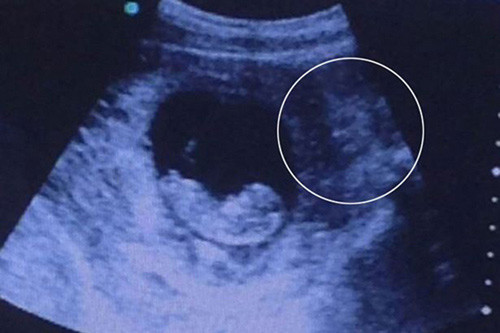

Cặp bố mẹ trẻ Amy Cregg và Leighton Hargreaves từ Accrington, Lancs nước Anh cảm thấy vô cùng tự hào và hạnh phúc khi hình ảnh chụp siêu âm cậu con trai Leo 31 tuần tuổi như nở nụ cười khi còn đang trong bụng mẹ.

Hiện tại, bố mẹ bé cho biết kể từ sau khi sinh đến nay đã 4 tháng tuổi, Leo thường xuyên nở nụ cười với mọi người, ngay cả trong lúc ngủ. Một công ty người mẫu nhí đã liên lạc với cha mẹ của Leo với mong muốn mua lại bức hình siêu âm nụ cười của cậu bé vì cảm thấy khá thú vị.